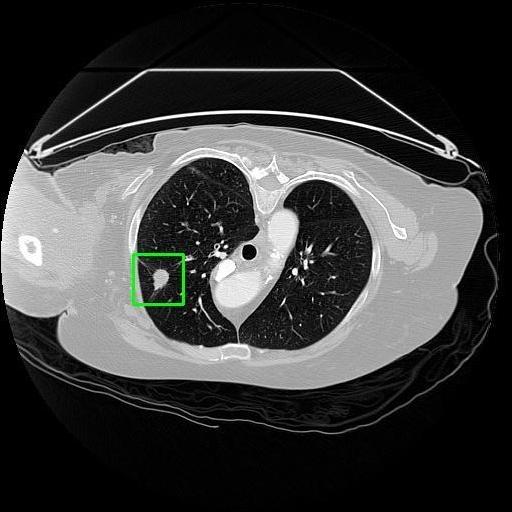

We developed an AI-based system using deep learning models for analyzing lung CT scans to detect and classify pulmonary nodules. We chose the YOLOv11 architecture for its enhanced object detection capability and adapted it specifically for medical imaging, incorporating pixel-level precision and severity classification.

Classification into three severity levels with colored bounding boxes.

Successfully built and deployed an AI model (YOLOv11) capable of detecting lung nodules in CT scans with high accuracy and real-time performance.

Designed a severity classification system that categorizes nodules into null, moderate, and severe using colored bounding boxes, assisting in rapid clinical decision-making.